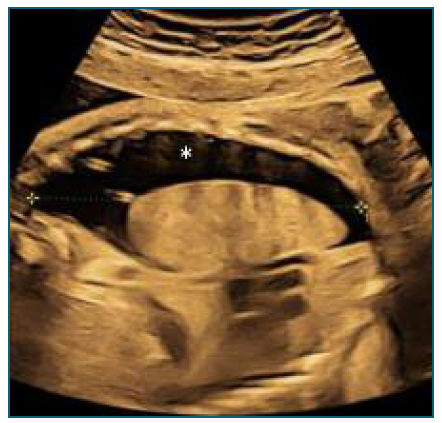

However, 12 hours after shunt placement, ultrasound showed a large right pleural effusion - Figure 4 (larger than before shunt placement - Figure 5). The ultrasound image suggested migration of the catheter into the thoracic cavity with atelectasis and reappearence of pleural effusion (Figure 6).

Considering the findings, the decision was made to terminate the pregnancy due to worsening pleural effusion, with thoracic drainage performed to facilitate ventilation in the postnatal period, prior to cesarean section.